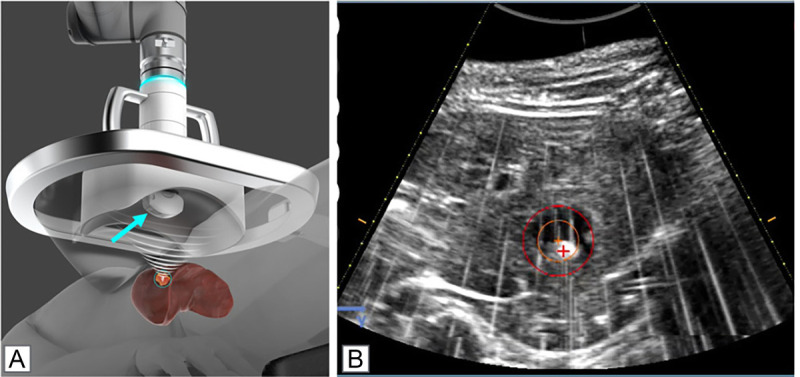

Abstract: Invasive open surgery used to be compulsory to access tumor mass to perform excision or resection. Development of minimally invasive laparoscopic procedures followed, as well as catheter-based approaches, such as stenting, endovascular surgery, chemoembolization, brachytherapy, which minimize side effects and reduce the risks to patients. Completely noninvasive procedures bring further benefits in terms of reducing risk, procedure time, recovery time, potential of infection, or other side effects. Focusing ultrasound waves from the outside of the body specifically at the disease site has proven to be a safe noninvasive approach to localized ablative hyperthermia, mechanical ablation, and targeted drug delivery. Focused ultrasound as a medical intervention was proposed decades ago, but it only became feasible to plan, guide, monitor, and control the treatment procedures with advanced radiological imaging capabilities. The purpose of this review is to describe the imaging capabilities and approaches to perform these tasks, with the emphasis on magnetic resonance imaging and ultrasound. Some procedures already are in clinical practice, with more at the clinical trial stage. Imaging is fully integrated in the workflow and includes the following: (1) planning, with definition of the target regions and adjacent organs at risk; (2) real-time treatment monitoring via thermometry imaging, cavitation feedback, and motion control, to assure targeting and safety to adjacent normal tissues; and (3) evaluation of treatment efficacy, via assessment of ablation and physiological parameters, such as blood supply. This review also focuses on sonosensitive microparticles and nanoparticles, such as microbubbles injected in the bloodstream. They enable ultrasound energy deposition down to the microvascular level, induce vascular inflammation and shutdown, accelerate clot dissolution, and perform targeted drug delivery interventions, including focal gene delivery. Especially exciting is the ability to perform noninvasive drug delivery via opening of the blood-brain barrier at the desired areas within the brain. Overall, focused ultrasound under image guidance is rapidly developing, to become a choice noninvasive interventional radiology tool to treat disease and cure patients.